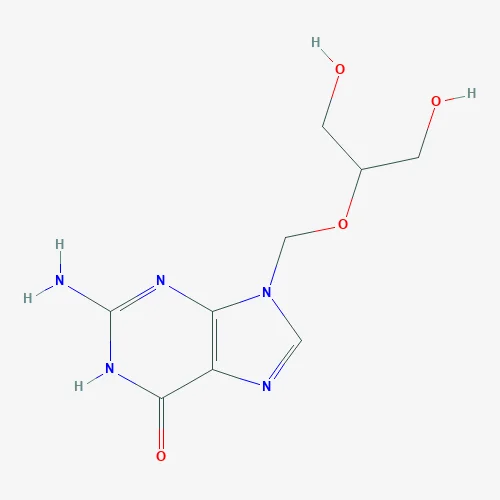

Factory outlet Exemestane / Exemesta / Aromasin 107868-30-4

Quick Details Port: Shanghai,Tianjin,Beijing,HK,Shenzhen Payment Terms: L/C,T/T,Western Union,MoneyGram,Paypal Supply Ability: 50.0 Kilogram/Kilograms per Month Other Names: Aromasin Usage: Animal Pharmaceuticals Sample: Freely Offered Purity: 2%-98% Appearance: White powder MOQ: 10 Grams Products name: Exemestane / Exemesta / Aromasin CAS No.: 107868-30-4 Assay: Aromasin Type: pharmaceutical intermediates Storage: Dry Storage CAS: 107868-30-4 EINECS No.: 643-090-2 Apperance: White Prowder MF: C20H24O2 Package: 1-2 Kg / Aluminum Foil Bag Application: Animal Pharmaceuticals Packaging Detail: Aluminum Bag; Drums;Paper Box Outside or as your request. Product Description Products Description: CAS 107868 30 4 Anti-Estrogen Exemestan powder 107868 30 4 Exemestan powder Exemestan Acatate Specifications: Appearance White crystalline powder Package 1kg/aluminium foil bag or as required Usage can be used as pharmaceutical material Minimum order quantity 10g passment Professional team special for package and shipment and staring on tracking code 24hours for customs pass guaranteed Shipping By express courier Shipping leading time Within 24 hours after receiving the payment Payment options Western Union, MoneyGram, T/T,Bank transfer shipping 1)Express delivery with DHL,EMS,Fedex,HKEMS,TNT,UPS (Express delivery within 24 hours after payment) 2)By sea (large quantity ,it will take 30-45days) Price Negotiated Supply ability 500kg/Month Exemestan Acatate COA: TEST ITEMS SPECIFICATION RESULTS Description : White Crystalline Powder […]